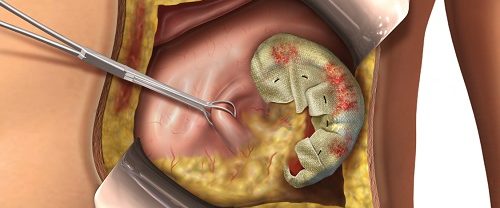

Vakumlu Aspirasyon Yöntemi İle Kürtaj Vakumlu Aspirasyon Yöntemi İle Kürtaj, istenmeyen gebeliğin sonlandırılması amacıyla yapılan tıbbi bir prosedürdür. Bu prosedür, gebelik dokusunun rahimden çıkarılması işlemidir. Vakumlu aspirasyon yöntemi, günümüzde yaygın olarak kullanılan modern bir kürtaj tekniğidir. Bu yöntem, etkili, güvenli ve hızlı bir şekilde gebeliğin sonlandırılmasını sağlar. Vakumlu Aspirasyon Yöntemi İle Kürtaj yöntemi, uterus içerisindeki…

Gebelik Takibi ve Doğum, bir kadının döllenmiş yumurtanın rahimde gelişmesi sürecidir. Ortalama olarak, gebelik yaklaşık 40 hafta sürer ve üç trimestre olarak bilinen üç aşamaya ayrılır. Gebelik Takibi ve Doğum Gebelik takibi, anne adayının ve bebeğin sağlığını izlemek için yapılan düzenli kontrolleri içerir. Bu kontroller, prenatal (hamilelik öncesi) ziyaretler, ultrason muayeneleri, kan testleri ve diğer…